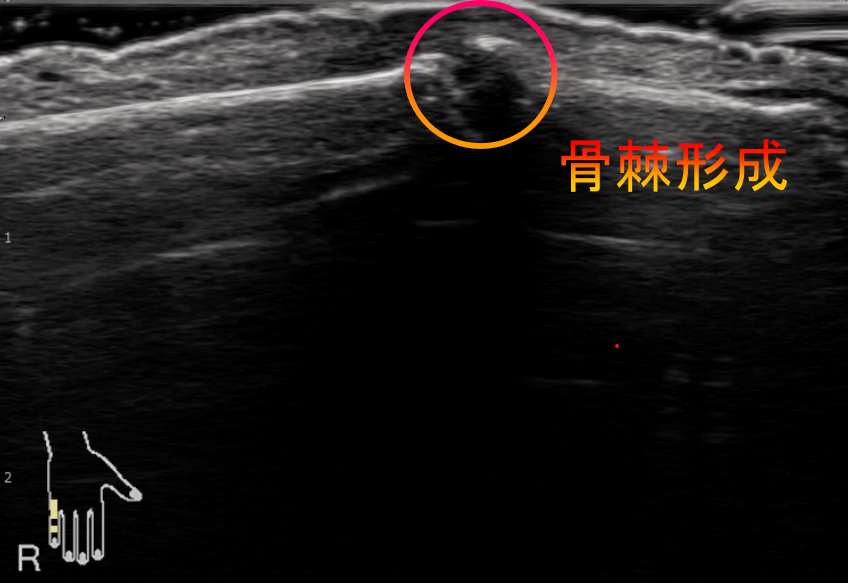

2つ目が、超音波検査です。

関節同士がぶつかることで出来る骨棘(コツキョク)が確認できます。

軟骨が磨り減ったり、骨棘が出来ることで、骨同士が当たることで、関節の痛みが出てきます。